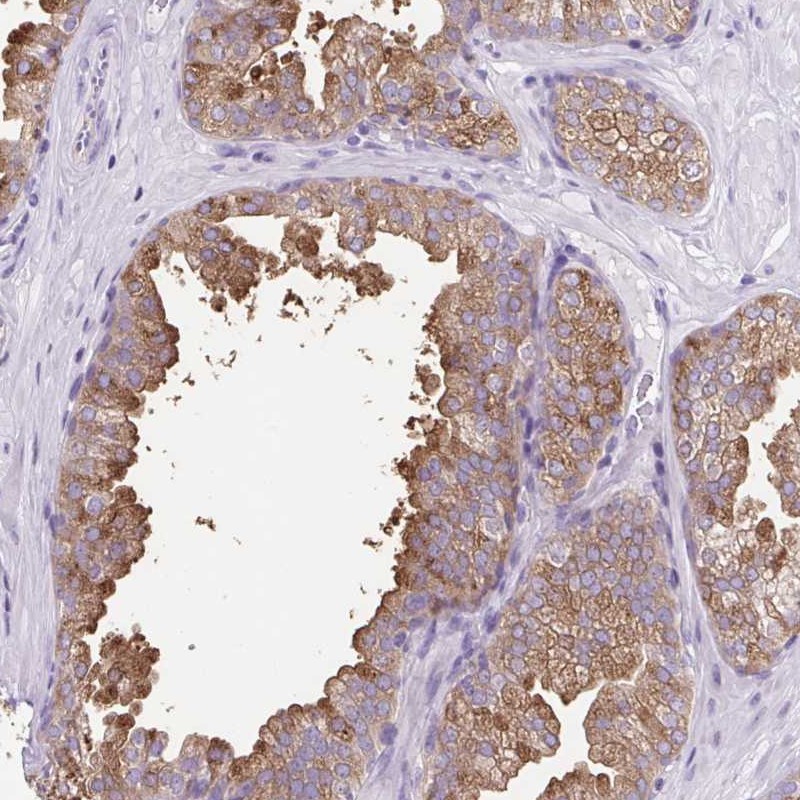

Immunohistochemical staining of human prostate shows moderate cytoplasmic positivity in glandular cells.